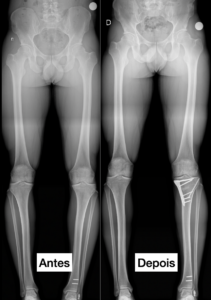

Tratamento cirúrgico:

O tratamento cirúrgico depende de cada caso. A deformidade pode ser corrida através de Osteotomia Corretiva, nos ossos ao redor do joelho ou nos ossos longos (fêmur e tíbia), ou deformidade pode ser corrigida na articulação do joelho através de Artroplastia Total, nos casos de artrose grave.

Osteotomia (correção do alinhamento)

Prótese de joelho (artroplastia) em casos avançados